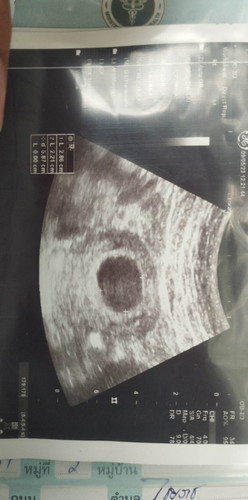

อัลตราซาวด์เจอถุงตั้งครรภ์แต่ไม่เจอตัวเด็ก

แม่ๆซาวด์เจอน้องกันตอนกี่wค่ะ บ้านนี้ซาวด์ตอน8wเจอแค่ถุงตั้งครรภ์ไม่เจอตัวเด็กหมอบอกมีโอกาสท้องลมอีก2สัปดาห์หมอนัดไปซาวด์อีกรอบค่ะ แบบนี้คงหมดหวังแล้วใช่ไหมค่ะ

เคยอ่านเจอว่ามีคนเห็นตัวน้องตอน 10w อยู่นะคะ ✌️✌️✌️